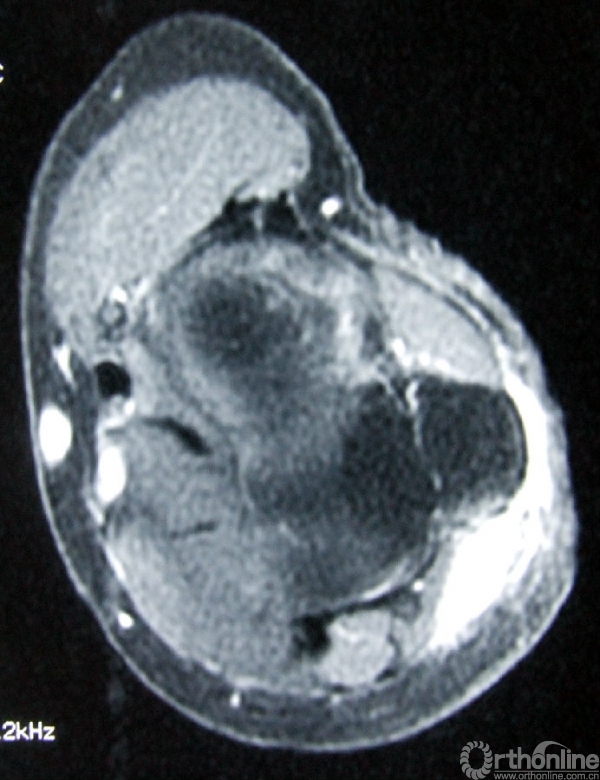

3.辅助检查:化验检查未见明显异常。B超显示右肘关节后方软组织内可见实性杂乱回声包块,1.5cm×1.0cm,界欠清,其内回声不均,可见少许血流信号。手术切口上端深处紧贴尺骨可见低回声小包块,0.9cm×0.2cm,未见血流信号。MRI(图2)示右肘关节后方皮下组织内可见软组织肿块影,边界不甚清楚,T1加权像呈现低信号,T2加权像呈中高信号,增强后T1加权像呈高信号,抑脂像亦呈现高信号。会诊病理(图3)显示成片较密集的轻度-中度间变的短梭形细胞,纤维性间质局部粘液变。初步考虑梭形细胞肉瘤Ⅱ级,可符合恶性外周神经鞘瘤形态。

图2a:T1加权像

图2b:增强后T1加权像

图2c:T2加权像

图2d:抑脂像